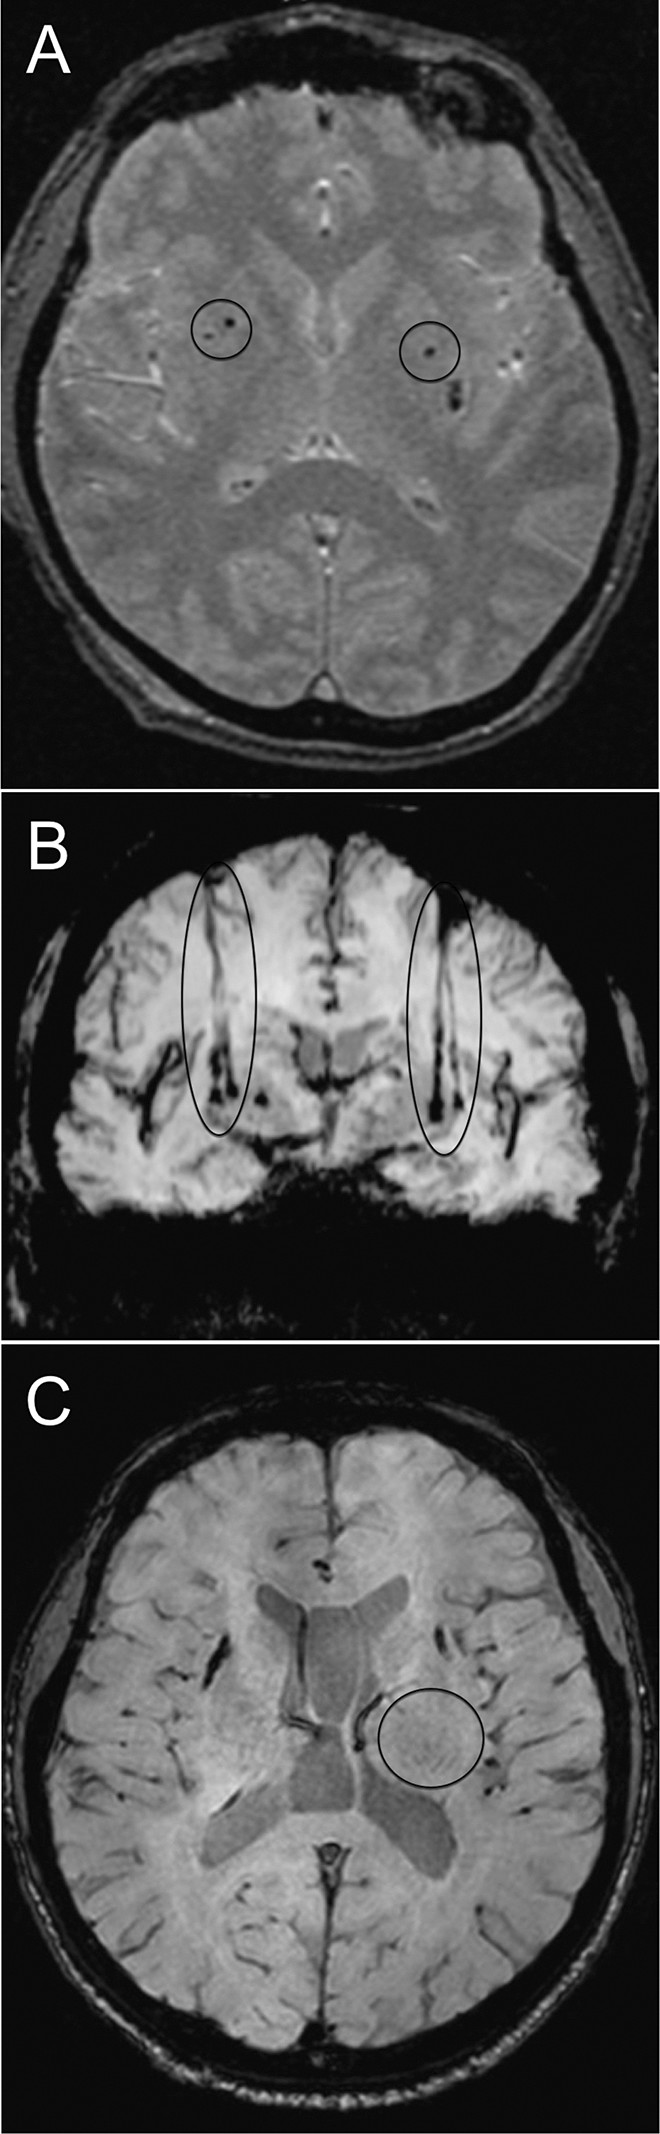

如圖2所示。細胞植入的位點和軌跡路徑如圖 1 和 2 所示。分別參見圖 2A 和 2B。在1、2和4年隨訪的幾個針跡結束時,在 T2 加權圖像上識別出小簇低信號。在 P4 的年度 MRI 監測中,在右側殼核(圖2C)中觀察到強大的移植物生長,沒有大腦結構的異常。未顯示腫瘤形成的證據。

圖2:移植患者的大腦MR圖像。